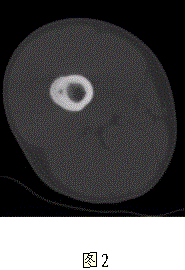

问题 患者男,17岁,右大腿外侧间歇性疼痛逐渐加重近3个月,夜间为重,X线片及CT示右股骨干下段外侧骨皮质梭形增厚硬化,增厚的骨皮质中心隐约可见小圆形低密度灶,骨髓腔未闭合,无外伤史(图1、2)。 为进一步确诊首选的影像学检查方法是

选项 A.增强CT B.薄层高分辨CT C.MRA D.DSA E.ECT

答案 B